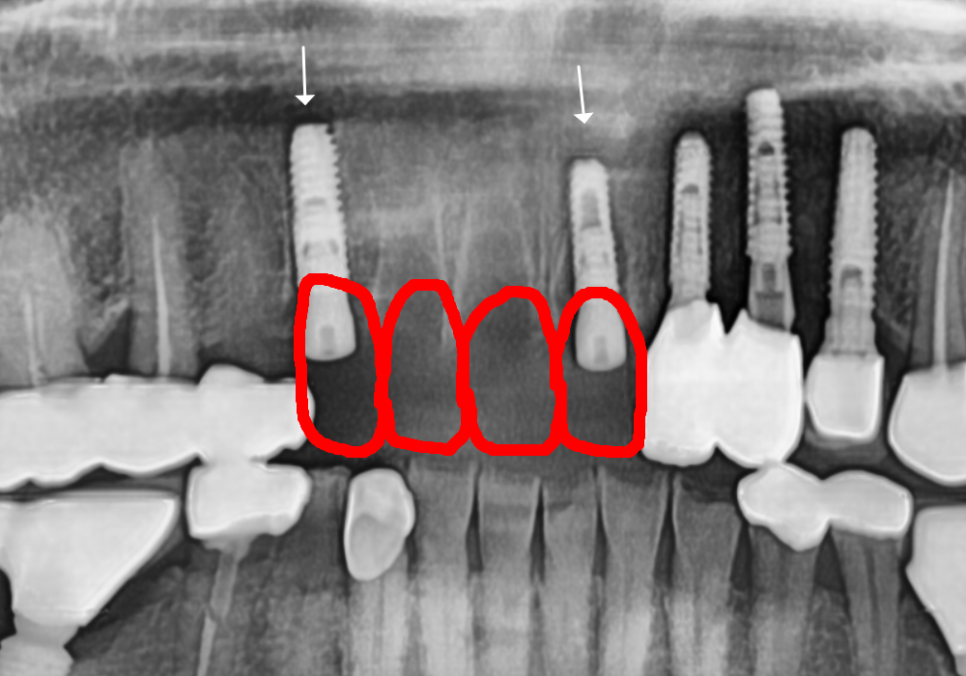

환자분께서는 다시 씌우기를 원하셨지만,

이미 충치 부위를 제거하고 나면

남아있는 치아량이 거의 없었습니다.

251020

이런 상태에서 억지로 기둥을 세워 씌운다 해도,

뿌리 끝 염증이 다시 문제를 일으키면

애써 만든 보철물을 금방 못 쓰게 될 게 뻔하죠...